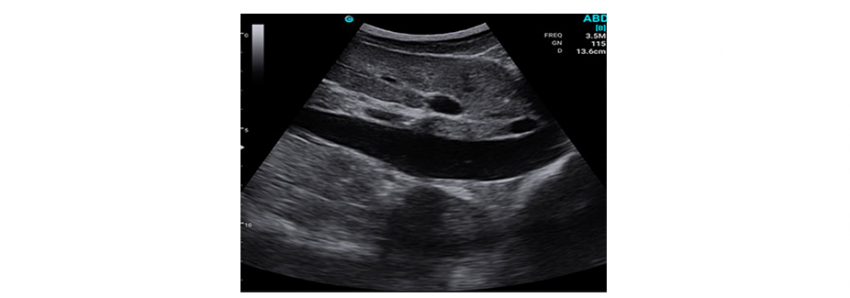

Here are some clinical images from which you can evaluate the quality of visualization and the interface of the program.

As for the Ramzed convex probe, there are usually default presets for wide abdominal examinations, prostate examinations, gynecological and obstetrical programs.

The clinical calculation package is available only for superficial obstetrical examinations (not for specialized examinations). As for the other programs, the usual calculations to measure the distance, area and volume of the structures are laid there.